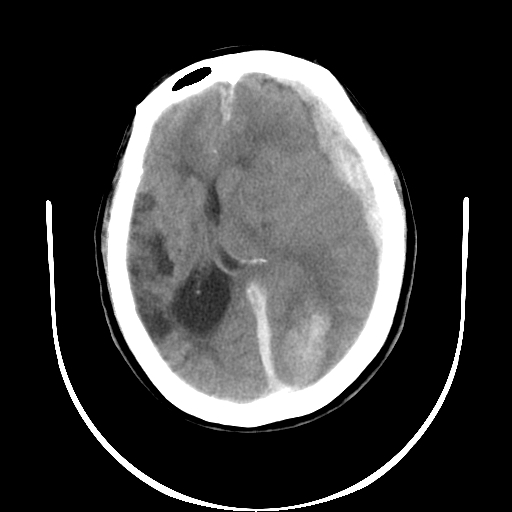

以下是引用gaoshengjiang在2007-10-7 9:18:00的发言:[br]左枕叶脑出血,左额颞顶部及纵裂硬膜下血肿,蛛网膜下腔出血,右颞叶脑梗塞。出血原因:患者年龄较大可能为动脉硬化或血管畸形?建议进一步临床检查。